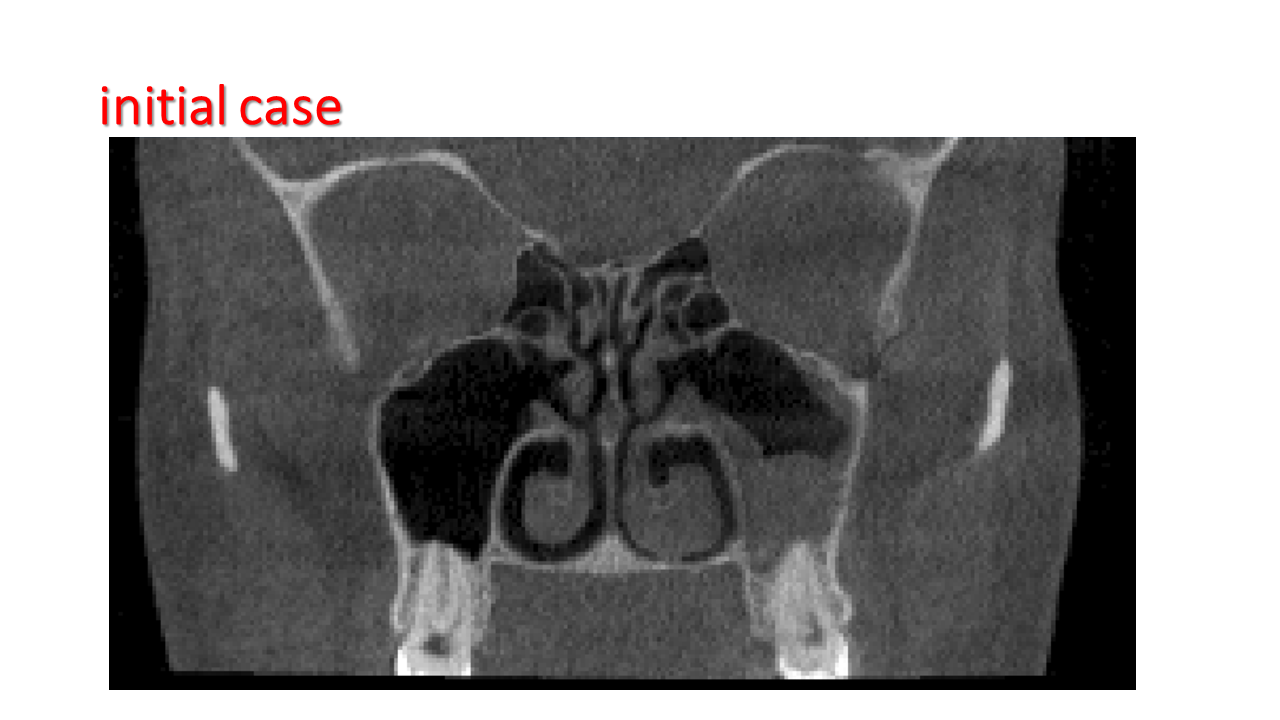

FESS Case Review and Radiologic Analysis (30.09.2016)

Case-based presentation focused on pre- and postoperative imaging in functional endoscopic sinus surgery (FESS). Includes anatomical landmarks, surgical variations, sinus pathology, and technique evaluation. Delivered by Dr. Levon Galstyan at AAOMFS.